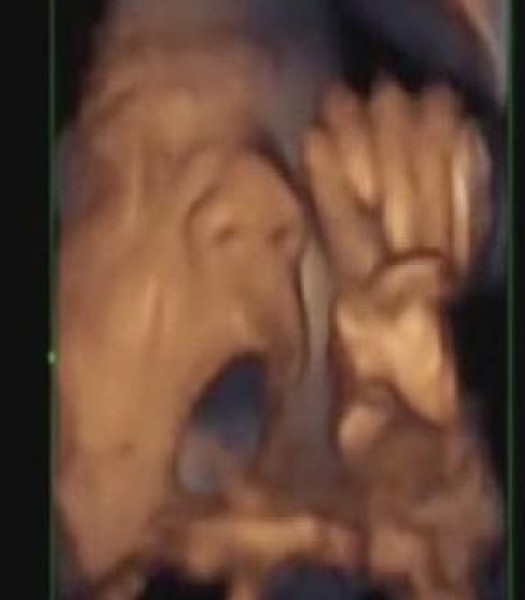

وأظهر فيديو بالأمواج فوق الصوتية جنيناً يتفاعل مع الموسيقى بتحريك فمه ولسانه فيما يبدو أنه يغني معها، وفق ما نشر "ديلي ميل".